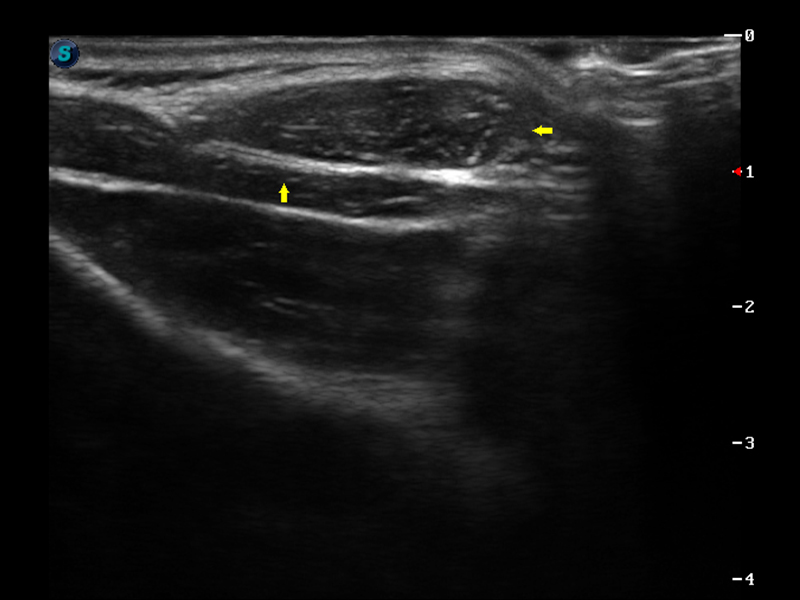

S9便携式彩色多普勒超声诊断仪是美狮贵宾会官网研发的高端便携彩超设备,外观设计新颖、产品性能卓越。S9在便携超声领域采用了突破传统的触摸屏交互设计,并以先进的软件硬件技术和设计理念,为您带来清晰的图像质量、稳定的工作性能和便捷的操作体验。

μ-Scan微米成像